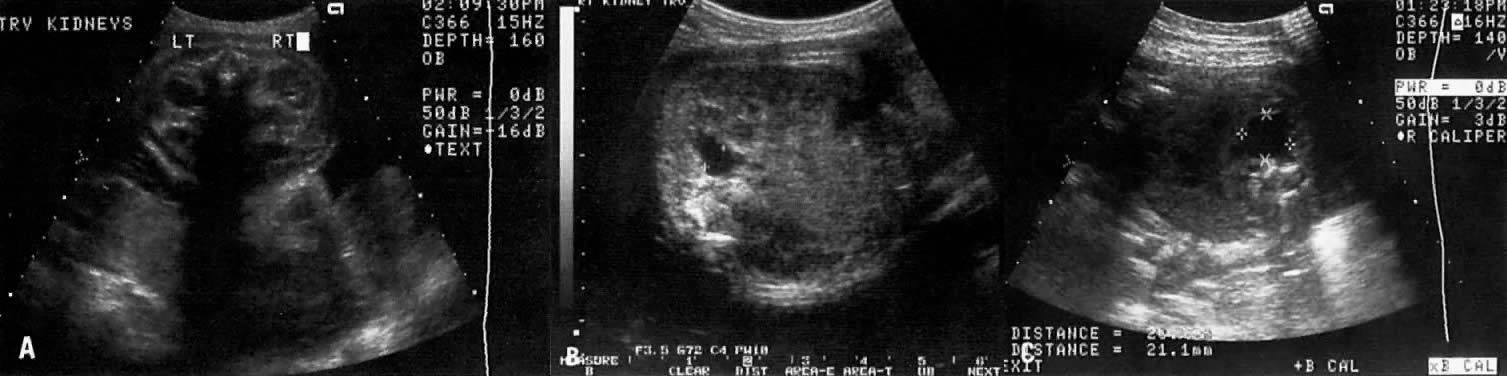

The Ureteropelvic Junction

Dilation of the UPJ (Fig. 14) results from (1) abnormal recanalization of the upper part of the ureter, resulting in varying degrees of obstruction; or (2) absence of the longitudinal muscle fibers in the upper ureter and renal pelvis. In the latter dysfunction, there is abnormal forward propulsion of urine, resulting in a dilation of the UPJ.46 Importantly, dilation of the UPJ may be associated with other anomalies involving the fetal cardiac, gastrointestinal, and central nervous systems.

Fig. 14. A. Cross-section of fetal abdomen at level of kidneys ( spine anterior ) show both kidneys. The left (LT) kidney shows dilation of the ureteropelvic junction (UPJ), but no hydronephrosis is present. B. The fetal spine is tot he left of the echogram and the kidney above the spine also shows dilation of the UPJ, the anteroposterior diameter (calipers) measuring 8 mm. C. The fetal spine is on the right lower side of the echogram. The kidney above the spine shows more severe UPJ (calipers) , with extension to the calyces.

Further, male fetuses are more frequently affected than female (5:1). The UPJ dilation also occurs more frequently on the left side and can be unilateral in 70% of cases.

Pyelectasis

The etiology of a dilated renal pelvis or pyelectasis is similar to that of a dilated UPJ. Reflux occurring at the level of the vesicoureteral valves also may result in pyelectasis (Fig. 15).

Fig. 15. Echogram showing a cross-section of the fetal abdomen at the level of the kidneys. The spine is anterior. Note bilateral pyelectasis (calipers). The anteroposterior diameter of each renal pelvis measure 5 mm.

The definition of mild or minimal pyelectasis in the literature is confusing.47 Further, the outcome of fetuses with minimal pyelectasis is not all “benign” as suggested in some studies.48 In fact, many such fetuses may require subsequent medical or surgical intervention. Thus, an anteroposterior diameter equal to or greater than 4 mm or 7 mm before and after 33 weeks' gestation, respectively, warrants postnatal follow-up.48

Moreover., approximately 3.3% of fetuses with pyelectasis in the range of 3 to 5 mm may also have chromosomal abnormalities, including Down syndrome.49, 50 Interestingly, 25% of fetuses with Down syndrome have pyelectasis, whereas only 2.8% of fetuses with a normal karyotype show this condition.49

Hydronephrosis

Dilation of the renal calyceal system results from abnormalities at a lower level of the urinary tract. It is differentiated from multicystic dysplastic disease by (1) ultrasonic visualization of radially placed calyces communicating with the renal pelvis and (2) preservation of some renocortical tissue (Fig. 16).

Fig. 16. Longitudinal echogram of fetus, showing kidney (within tracing) with extensive hydronephrosis. Many dilated calyces are communicating with the renal pelvis, a finding that differentiates hydronephrosis from multicystic kidney.

In utero diagnosis of pyelectasis, UPJ dilation, and hydronephrosis is significant because it identifies fetuses who will require postnatal urologic evaluation. As a result, early surgical intervention or medical treatment with antibiotics will prevent irreversible renal compromise.

Intravenous administration of furosemide (40 mg IV) has not been helpful in differentiating renal agenesis from severe intrauterine growth restriction. Further, because of associated oligohydramnios as well as an enlarged adrenal gland that mimics renal appearance, the diagnosis by gray scale ultrasound is difficult (sensitivity, 50%).51 In suspected cases, however, the use of color Doppler velocimetry may show absence of renal arteries in bilateral renal agenesis and only one renal artery in the unilateral form of this abnormality (Fig. 17).52

Fig. 17. A. Cross-section of fetal abdomen at level of kidneys (spine anterior, arrow) shows both kidneys. The areas on each side of the spine are filled with a uniform echopattern, and no kidneys are seen. B. Color Doppler of aorta in a fetus with renal agenesis fails to outline renal arteries.

The etiology is related to either (1) poor induction of nephron formation or (2) obstructive uropathy. Defects in nephron formation occur early in embryogenesis, thus impeding renal development. In such cases, the kidneys are very small, each weighing as little as 1 g, and cysts are evident only via microscopic examination. This defect is classified as Potter type II-B dysplastic kidney.55 If the defect develops by 9 to 13 postmenstrual weeks, the fetal kidney assumes a large multicystic appearance (Potter type II-A; Fig. 18).

Fig. 18. Cross-section of fetal abdomen at level of kidneys (spine anterior) shows both kidneys. Note pyelectasis of right kidney (anteroposterior diameter = 6.4 mm). The left kidney is enlarged and uniformly cystic, with no apparent renal cortical tissue, which is characteristic of multicystic kidney.